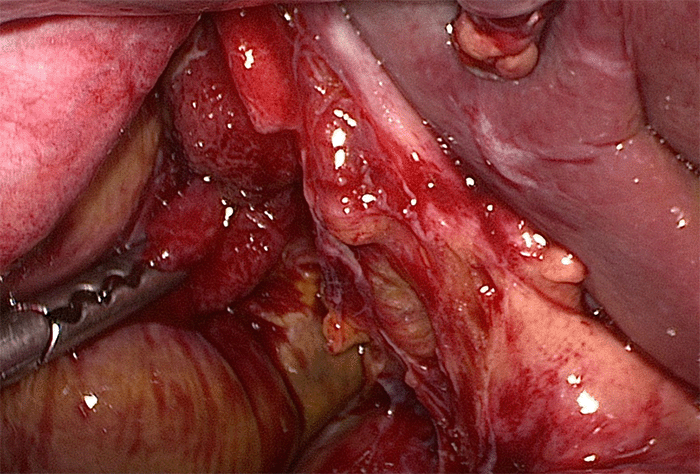

Figure 4. Intraoperative Image. Published with Permission

Note perforation at the junction of infundibulum and cystic plate; laparoscopic grasper pointing to rupture

The patient was taken for diagnostic laparoscopy, which revealed a 3 cm perforation of the gallbladder at the level of the infundibulum along the cystic plate with biliary peritonitis (Figure 4). Abdominal washout was undertaken with copious irrigation, and a laparoscopic cholecystectomy was completed without complication. The postoperative course was uneventful, and the patient was discharged two days later.